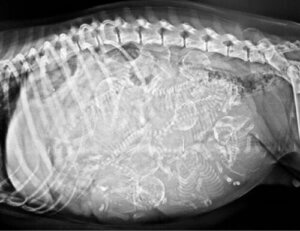

Den 6. februar 2021 blev en kyklop hund født på Filippinerne (Aklan), som det blev rapporteret af den digitale avis TimesNoNews. Dyrets mor fødte to hvalpe. En af dem var helt normal, og den anden havde den allerede nævnte cefale mutation. Som du nok kan forestille dig, var udsigterne for den lille kyklop ikke særlig lovende.

Hvalpens fremtoning kunne ikke have været mere atypisk. Denne hund var lille med en hvid pels og havde et kæmpe øje i panden og to store tunger, der stak ud fra hver side af munden. Da øjet optog så meget plads, havde hundens cefale struktur ingen næse eller snude.

Uheldigvis havde denne hund store problemer med vejrtrækningen fra det øjeblik, den blev født. Da den ikke var i stand til at klare sig selv, tog hundens ejer den med til dyrlæge i håb om, at den ville klare den med den rette behandling. Som forventet døde hunden til sidst omkring klokken 22 den samme dag på grund af vejrtrækningsproblemer.